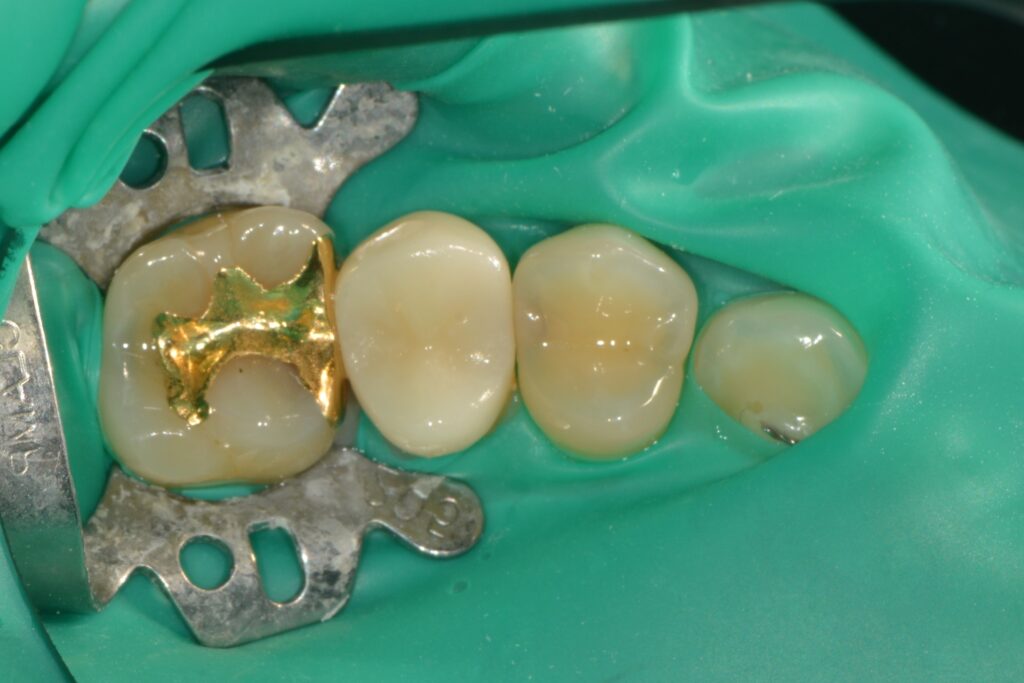

[치근우식] 잇몸 경계 부위가 썩었을 때, 왜 ‘러버댐’이 필수일까요? (Feat. 자연치아 살리기)

#치근우식#러버댐#isodam